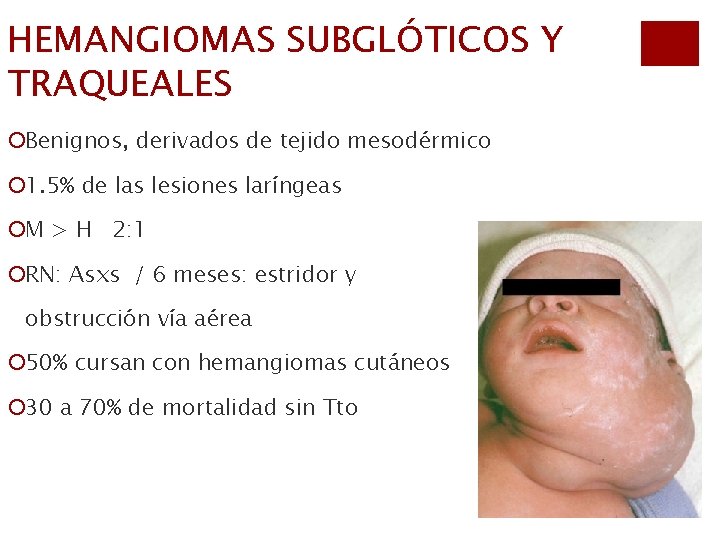

HEMANGIOMAS SUBGLÓTICOS Y TRAQUEALES ¡Benignos, derivados de tejido mesodérmico ¡ 1. 5% de las lesiones laríngeas ¡M > H 2: 1 ¡RN: Asxs / 6 meses: estridor y obstrucción vía aérea ¡ 50% cursan con hemangiomas cutáneos ¡ 30 a 70% de mortalidad sin Tto

Dx: ¡Clínica: estridor progresivo y retracciones ¡Lesiones asimétricas, cubierta por mucosa lisa ¡IRM: estrechez subglótica asimétrica, efecto de masa ¡Endoscopia: lesión compresiva, asimétrica, coloración rojiza-azulada, mas frec en cara postlat.